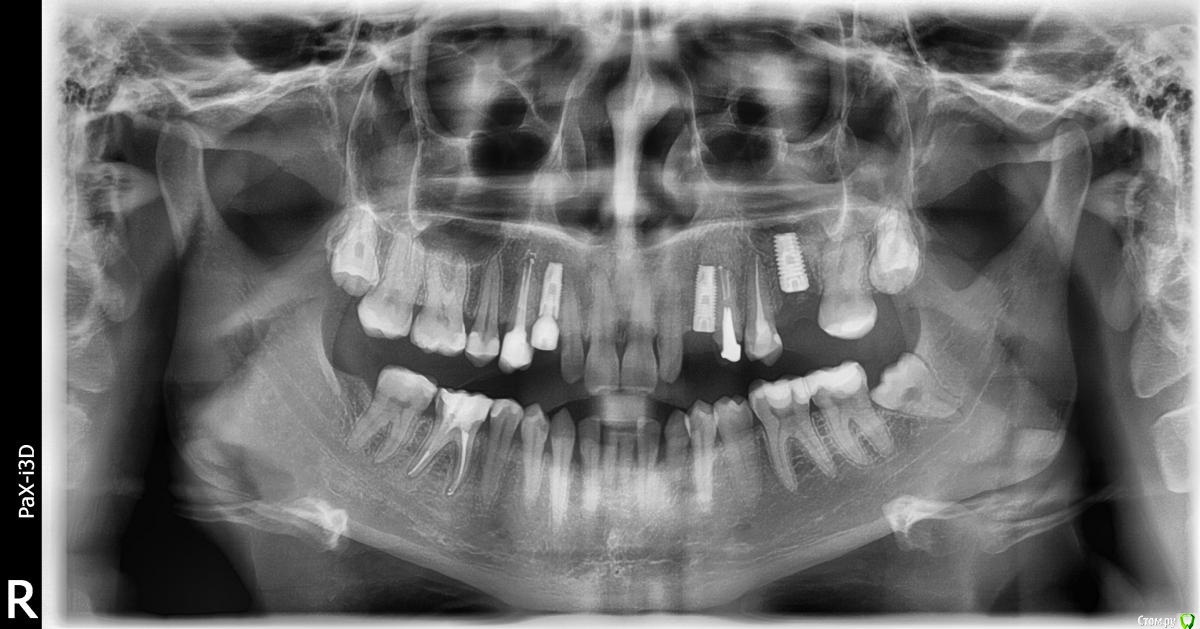

fifa888.dexo Опубликовано 20 июня, 2016 Поделиться Опубликовано 20 июня, 2016 (изменено) Здравствуйте можно ли по этому снимку сказать суставы на месте или нет?http://s019.radikal....0067e02b79c.png Изменено 20 июня, 2016 пользователем fifa888.dexo Ссылка на комментарий

fifa888.dexo Опубликовано 20 июня, 2016 Автор Поделиться Опубликовано 20 июня, 2016 (изменено) а вас чтото беспокоит?до постановки коронок не беспокоило ничего вообще,ходила с временными и вообще не знала о суставах ничего,после постановки моя жизнь превратилась в ад.Первые две недели было просто неудобно,не знала куда пристроить челюсть,потом начался хруст,скрип,щелканье,боль и закладывание в ушах,,один раз заклинило шею и очень болела голова,по городу ортопеды сказали занижен прикус то ли с одной то ли с обеих сторон,через месяц ношения челюсть перекосило вправо.В этот же день мое терпение кончилось,и я настояла переделать все как было на временных,очень внимательно отнеслась к подтачиванию.В первые сутки прошла острая боль и давление в голову,челюсть восстанавливалась неделю.Первые два дня пила найс,потом делала упражнения из интернета. На данный момент все встало на место практически,я могу более менее спокойно расслабить и сомкнуть челюсть,но чувство, что с одной стороны нагрузка больше все равно осталось. Записана к другому ортопеду по совету моего же ортопеда,на консультацию,у него есть аксиограф итд. Терзают сомнения что коронки были или завышены или занижены и моя челюсть тут не при чем)))К слову коронки были на 4-ах,т.е на своих зубах.Когда были временные,которые я носила год, мне одели на шестой зуб(имплант) сначала постоянную,все было нормально,но когда одели на четверки постоянные а потом на шестой,то коронка показалась что мешала и ее точили еще.Ах да,зуб справа внизу шестой был выведен из прикуса до имплантации,то теперь я чувствую полноценную опору на него,зуб слева вверху пятый никогда не касался антагониста внизу,но теперь он стирается изнутри иногда слышу там хрустит как песок. Пы.сы. Сегодня мне снился сон,что у меня вставная челюсть и мне больше не надо ни о чем думать и ничего мне не мешает итд)))))) Изменено 20 июня, 2016 пользователем fifa888.dexo Ссылка на комментарий